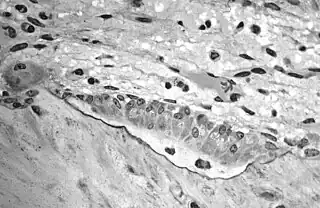

En histología, el osteoide es la porción orgánica sin mineralizar de la matriz ósea que se forma con anterioridad a la maduración del tejido óseo. Los osteoblastos comienzan el proceso de formación tisular del hueso secretando el osteoide como varias proteínas específicas. Cuando el osteoide se mineraliza, este mismo y las células del hueso adyacentes se han convertido en tejido óseo nuevo.

El osteoide conforma aproximadamente el 50% del volumen óseo y el 40% del peso de los huesos está compuesto de fibras y sustancia fundamental. El tipo de fibra predominante es el colágeno tipo I; consta del 90% del osteoide. La sustancia fundamental está formada de sulfato de condroitina y osteocalcina.

- Imagen de histología: 69_03 en la Universidad de Oklahoma - Centro de Ciencias de Salud - "Hueso, fémur"